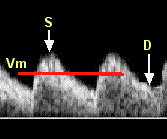

S = systolic peak (maximum velocity); the maximum velocity during contraction of the fetal heart.

D = end-diastolic flow; continuing forward flow in the umbilical artery during the relaxation phase of the heartbeat.

Vm = mean velocity.